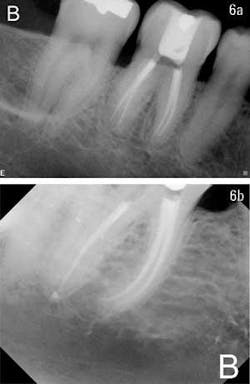

Once the cone has been inserted and verified with a digital image or X-ray, it is recommended to sear off the cone at the orifice and to remove an additional 1 to 2 millimeters of gutta percha from the canal. At this point, simply place Activ GP sealer on top of the cone to act as a canal cap. Some dental schools in North America actually recommend covering the entire chamber floor with glass ionomer to prevent leakage. This is the clinician’s choice, but it is highly recommended to place a final canal cap on top of the obturated canal. If retreatment is ever necessary, the caps are easily removed with an ultrasonic. However, if the patient loses the temporary filling, he or she has not lost the root canal. This is very important because experience has shown us that often a patient has the endodontics completed, yet has exhausted most of his or her insurance coverage for the year. Consequently, the patient walks around for a long time (up to a year) before having the tooth properly restored (figures 6a and 6b).